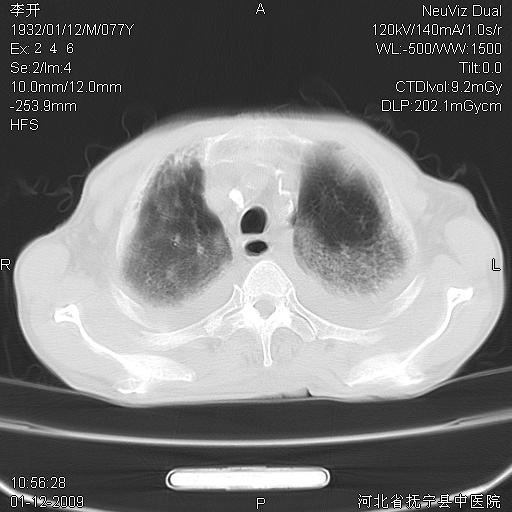

以下是引用黑白光影在2009-1-19 16:49:00的发言:[br]心衰肺水肿;心包、胸腔积液;冠脉钙化;肺部感染。